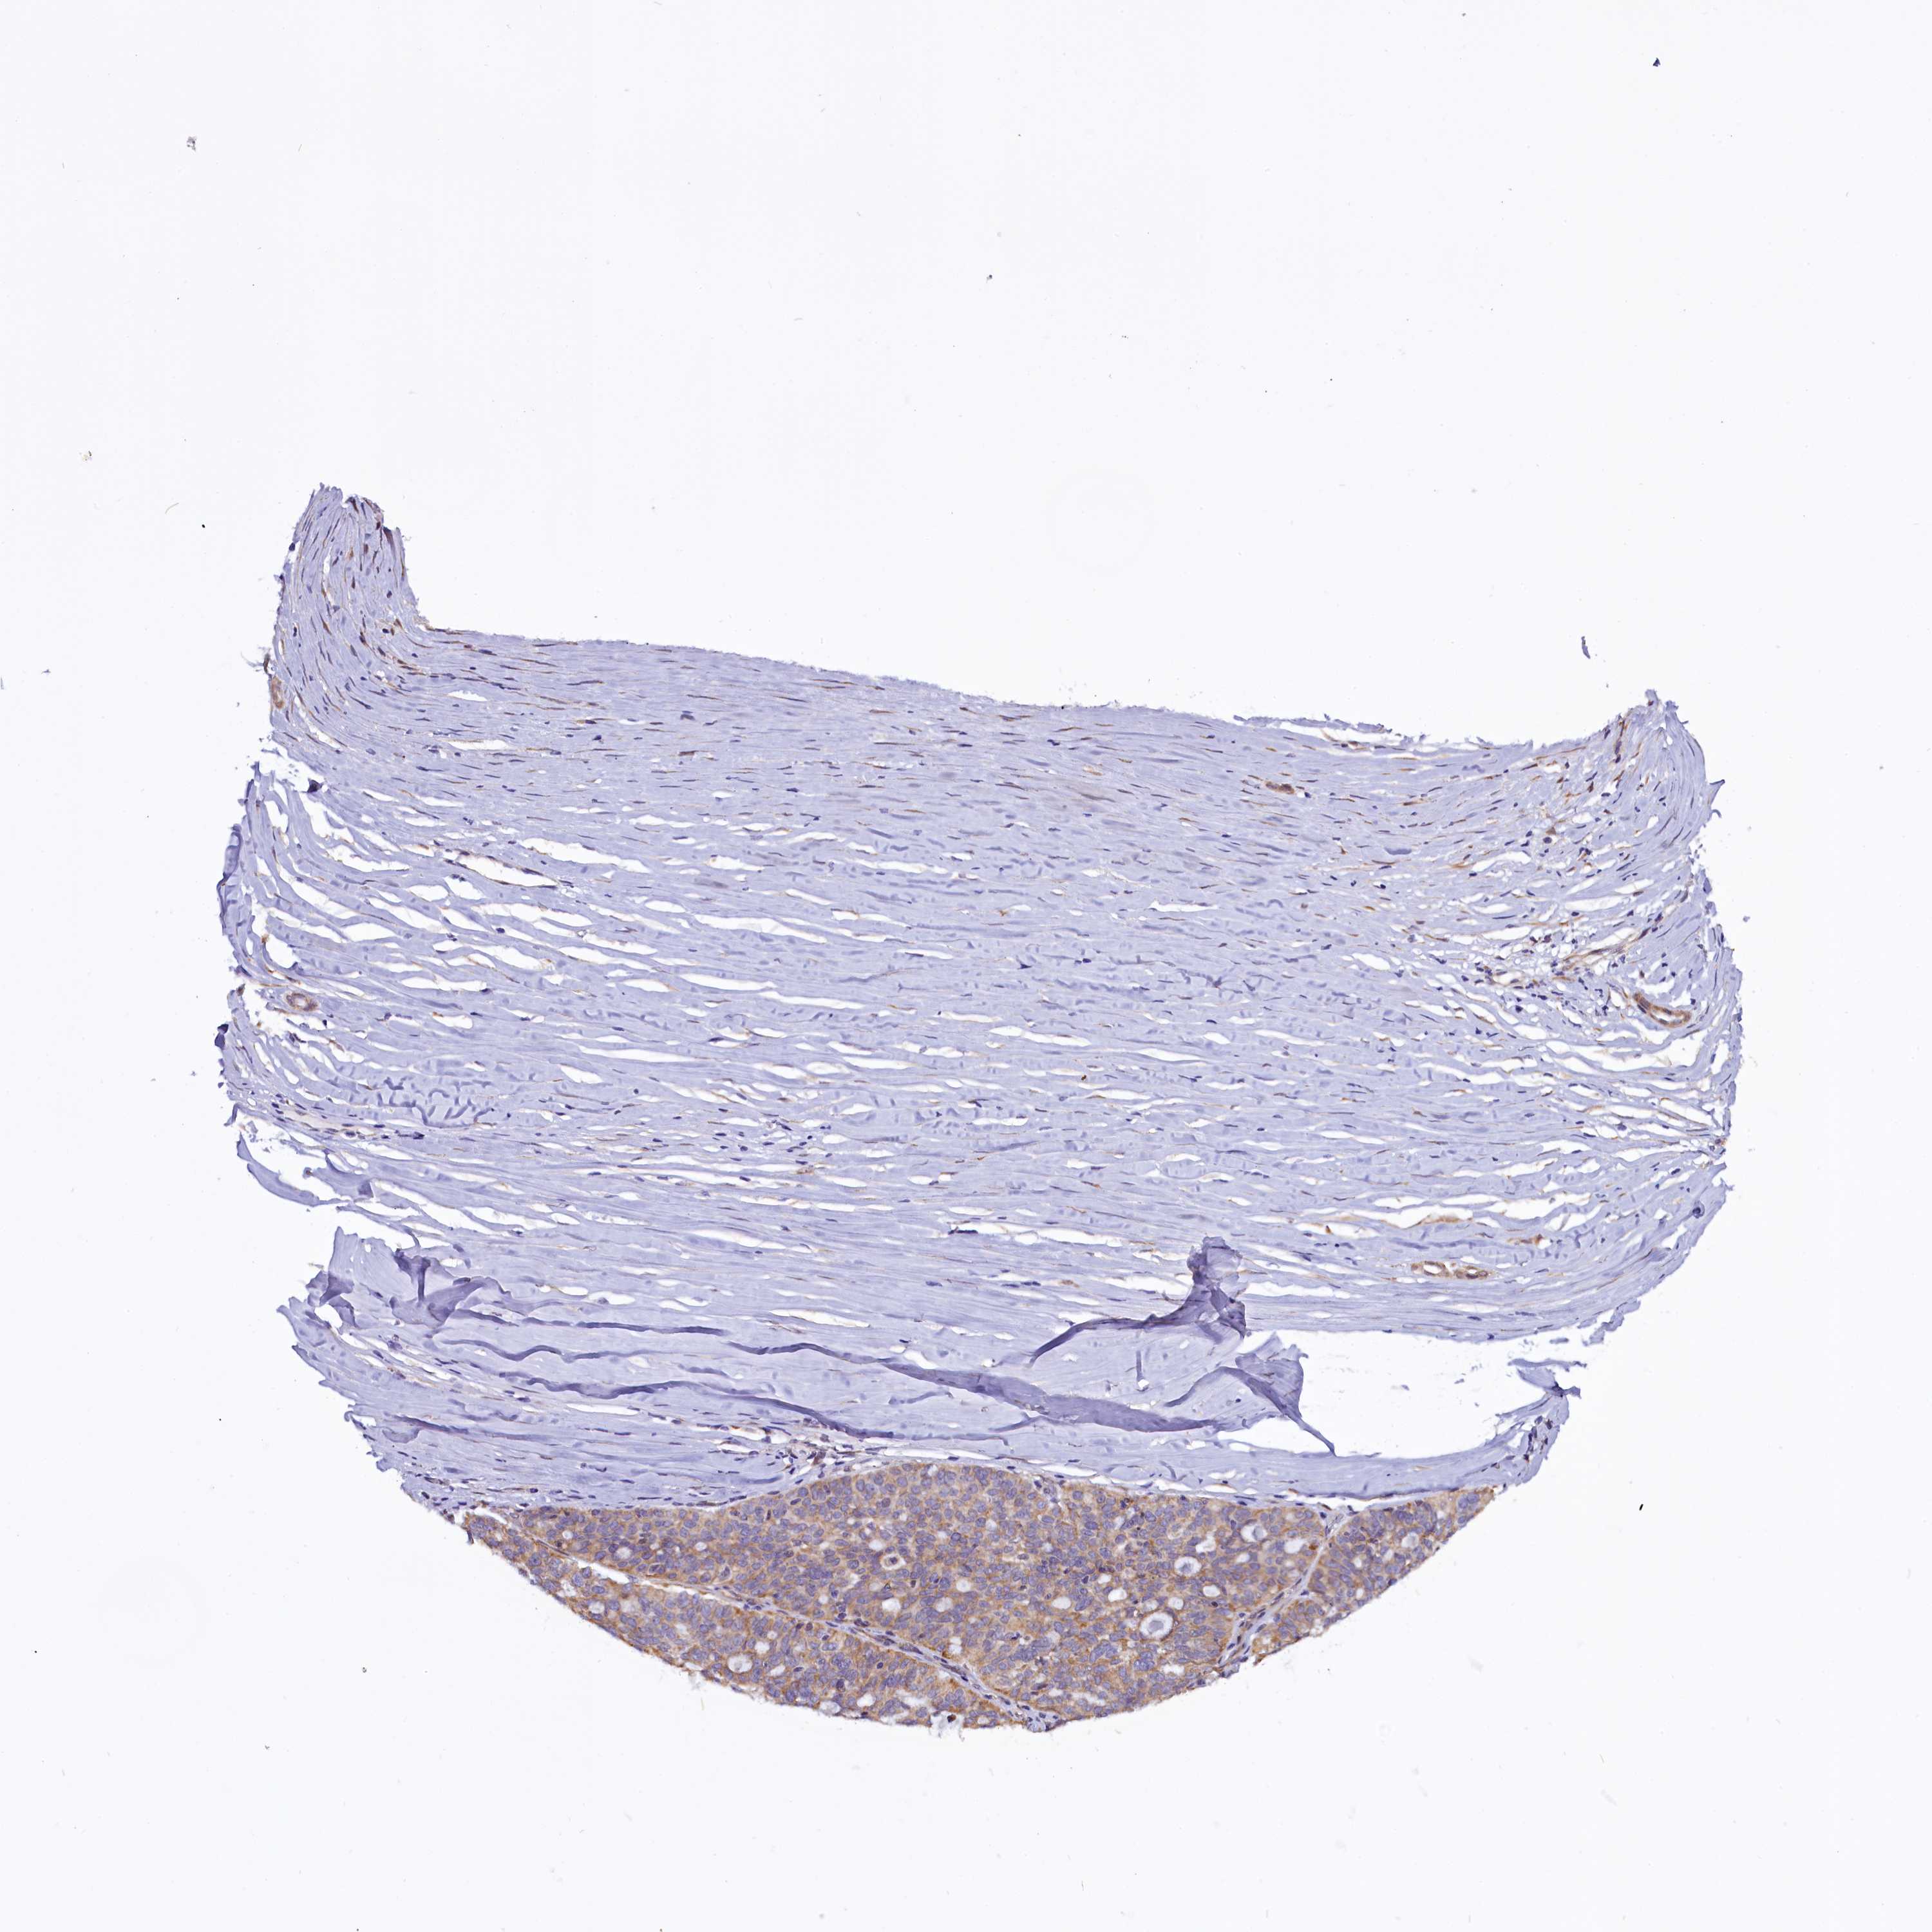

OVARIAN CANCER - Protein expressioni

A mouse-over function shows sample information and annotation data. Click on an image to view it in a full screen mode. Samples can be filtered based on level of antibody staining by selecting one or several of the following categories: high, medium, low and not detected. The assay and annotation is described here.

Note that samples used for immunohistochemistry by the Human Protein Atlas do not correspond to samples in the TCGA dataset.

Antibody stainingi

Antibody staining in the annotated cell types in the current human tissue is reported as not detected, low, medium, or high, based on conventional immunohistochemistry profiling in selected tissues. This score is based on the combination of the staining intensity and fraction of stained cells.

Each image is clickable and will lead to virtual microscopy that enables deeper exploration of all samples and also displays staining intensity scores, fraction scores and subcellular localization as well as patient and tissue information for each sample.

Antibody HPA041412

Antibody HPA056006

Cystadenocarcinoma, serous, NOS

Carcinoma, endometroid

Cystadenocarcinoma, mucinous, NOS

Carcinoma, NOS